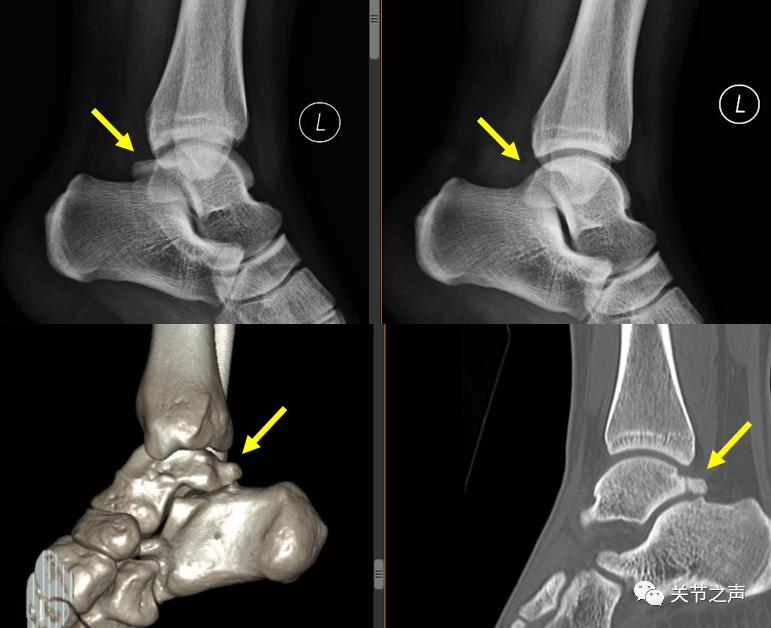

所谓后踝关节撞击综合征,是指踝关节在强迫跖屈时产生后踝关节疼痛,疼痛大多偏内侧,最常见的原因是距骨后方突起的解剖异常,如三角骨(非融合距骨二次骨化中心)和Stieda突出(一个距骨后外侧突的骨突)。这个向后突出的骨块大多是先天形成的,也可因外伤或过度使用而形成。

3.拍X片是否有距骨三角骨存在,B超或MRI检查是否显示踇长屈肌腱骨性卡压、腱鞘狭窄、腱鞘积液、滑膜增厚等。